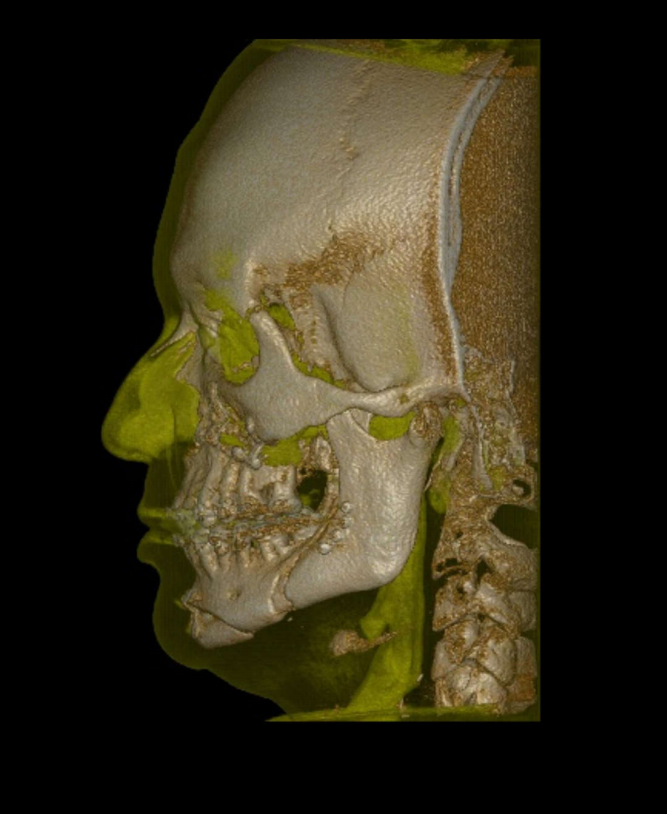

TC de face (do Hióide à Glabela), reconstrução 3D do tecido ósseo, radiografia panorâmica, telerradiografia lateral com traçado, cortes transversais e axial de maxila e mandíbula e arquivo DICOM- entregue em pasta de Pvc.

TC de face (do Hióide à Glabela), reconstrução 3D do tecido ósseo, radiografia panorâmica, telerradiografia lateral e frontal com traçado, cortes transversais e axial de maxila/mandíbula e arquivo DICOM – entregue em pasta de Pvc.

TC de face (do Hióide à Glabela), reconstruções 3D do tecido mole/ósseo/vias aéreas, radiografia panorâmica, telerradiografia lateral e frontal com traçado, cortes transversais e axial de maxila/mandíbula, ATM e arquivo DICOM – entregue em pasta e caixa de Pvc.